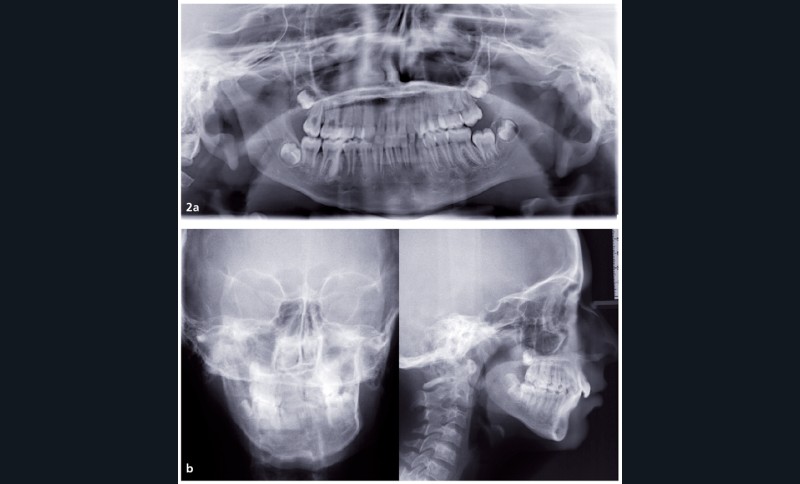

Analyse squelettique : les documents montrent une classe II squelettique modérée par rétrognathie mandibulaire dans un contexte de normodivergence. Les examens complémentaires confirment que la latérognathie mandibulaire gauche est la conséquence d’un hypo-développement des structures maxillaires et mandibulaires de ce même côté (fig. 2a, b et c). On observe sur les reconstructions 3D (à partir des coupes scanner) à l’aide du logiciel Osirix® : un corps mandibulaire fin, un ramus peu développé, un col du condyle grêle.